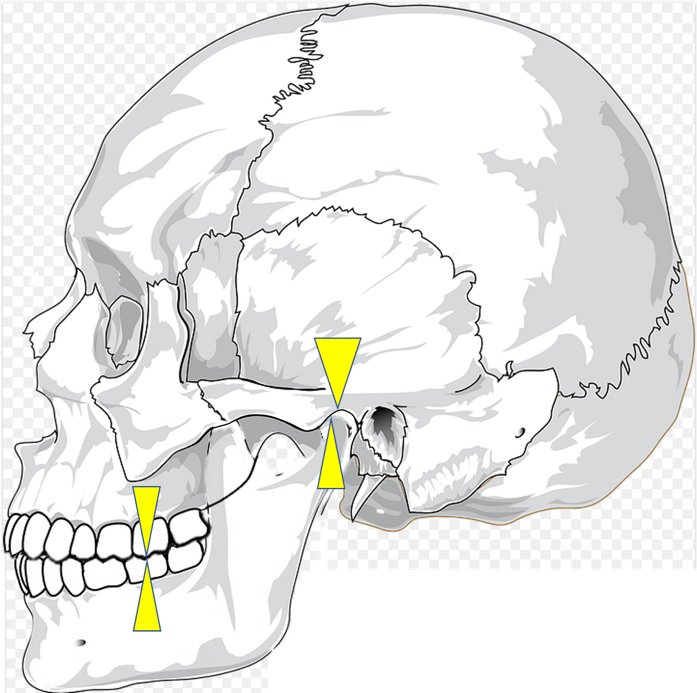

しかし、図のように、歯がかみ合ったときに、顎の関節に負担がかからない状態であれば良いのですが、

このように、歯をかみ合わせたら、顎の関節がずれてしまう人がいます。

そしてのこの方は顎の関節がラクな位置で咬むと、このようになります。顎関節はラクですが、歯の凸凹がかみ合っていないので、まともに、ものを咬めません。よって、顎に負担をかければギリギリ咬める、という状況であれば、人間は顎の関節よりも、「ちゃんと咬む」ことを優先して、食物を咀嚼してしまいます。結果、顎の関節には、負荷がかかり、人によっては顎関節症になる可能性が出てきます。

先ほど説明した、このかみ合わせの位置を中心位、といいます。